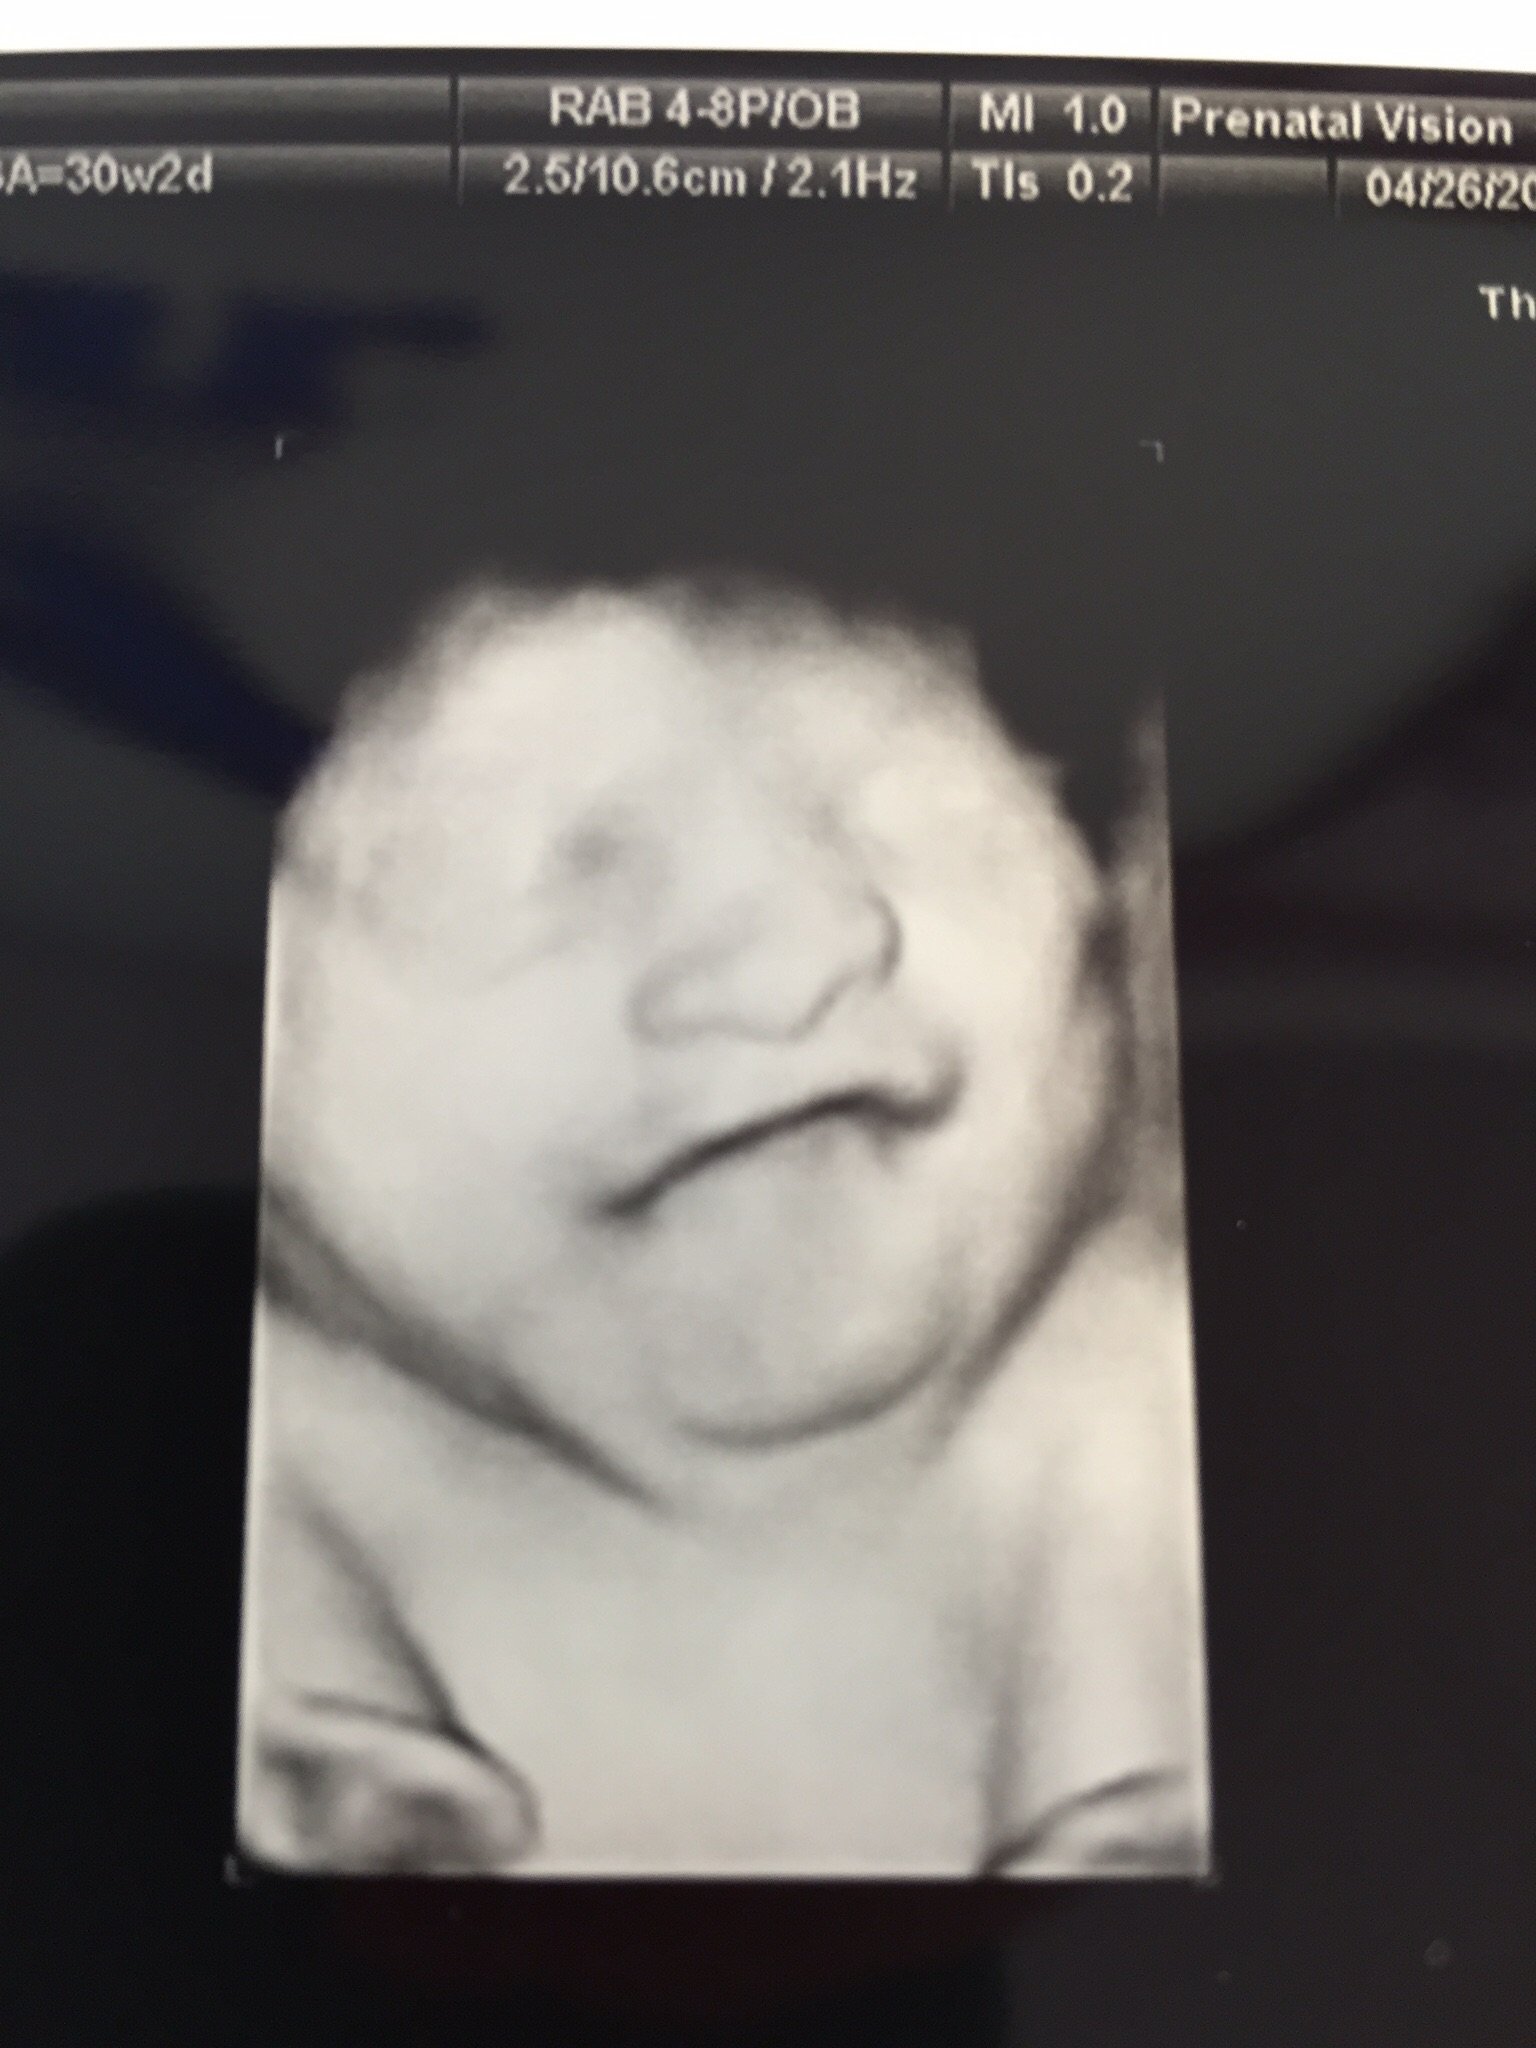

at my ultrasound my baby was constantly sticking her tongue in and out. They tech smiled when she pointed it out. The baby did it for the entire 5 - 10 minutes we were in there. Did anyone else's baby do this? I'm assuming she was just tasting the amniotic fluid as I had just had a sweet drink 30 min before. Any thoughts?